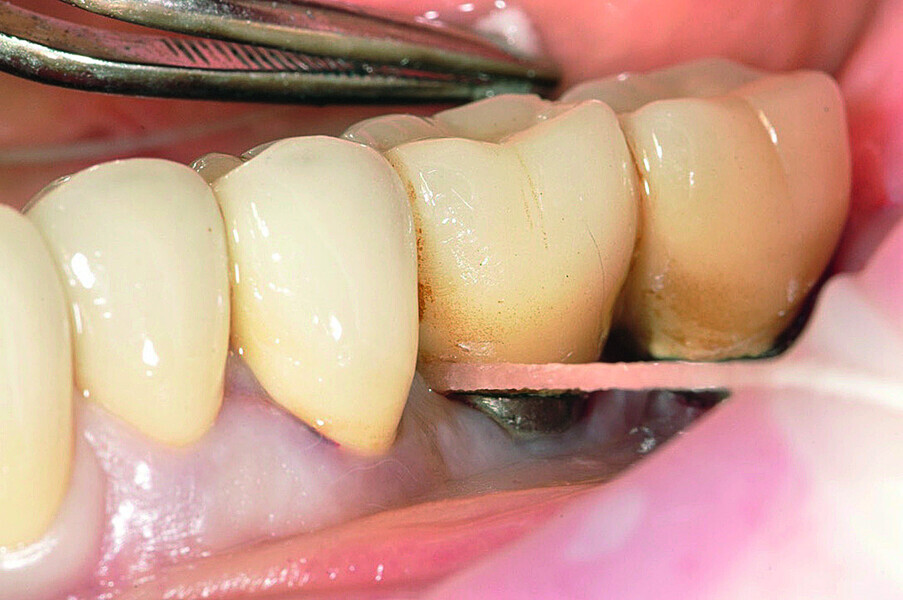

Fig. 3: Excess resin cement around the implant.